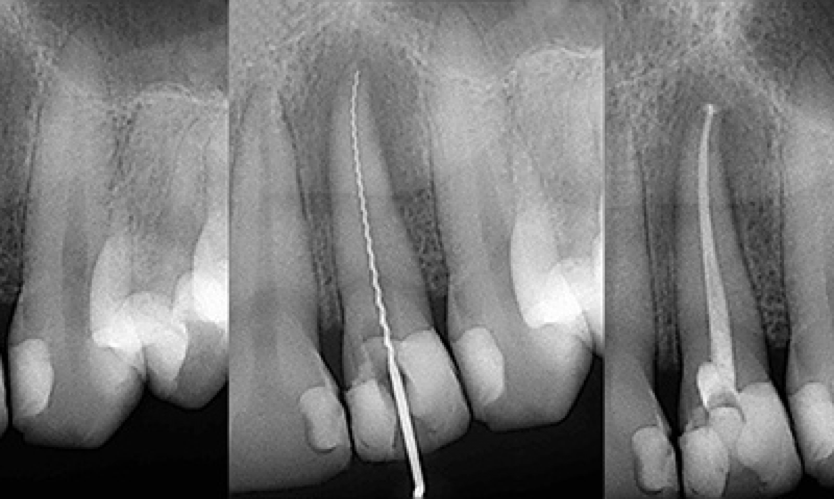

Root Canal Therapy